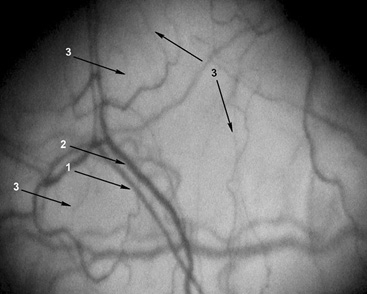

Для иллюстрации материалов на рис. 1–3 представляем фрагменты МЦР бульбарной конъюнктивы некурящего, курящего и прекратившего курить пациентов с АГ.

Рис. 1. Фрагмент микроциркуляторного русла конъюнктивы. Увеличение ×96. Пациент П. 44 лет, не курит. Страдает артериальной гипертензией 3-й степени, риск 4, в течение 10 лет. Артериальное давление на момент исследования 137/90 мм рт.ст., пульс 63 в минуту. 1 — артериола (d=18,8 мкм); 2 — венула (d=37,2 мкм), артериоло-венулярный коэффициент 0,5; 3 — капилляры (d=9,3 мкм), количество капилляров на 1 мм2 поверхности конъюнктивы 5,7 ед./мм2